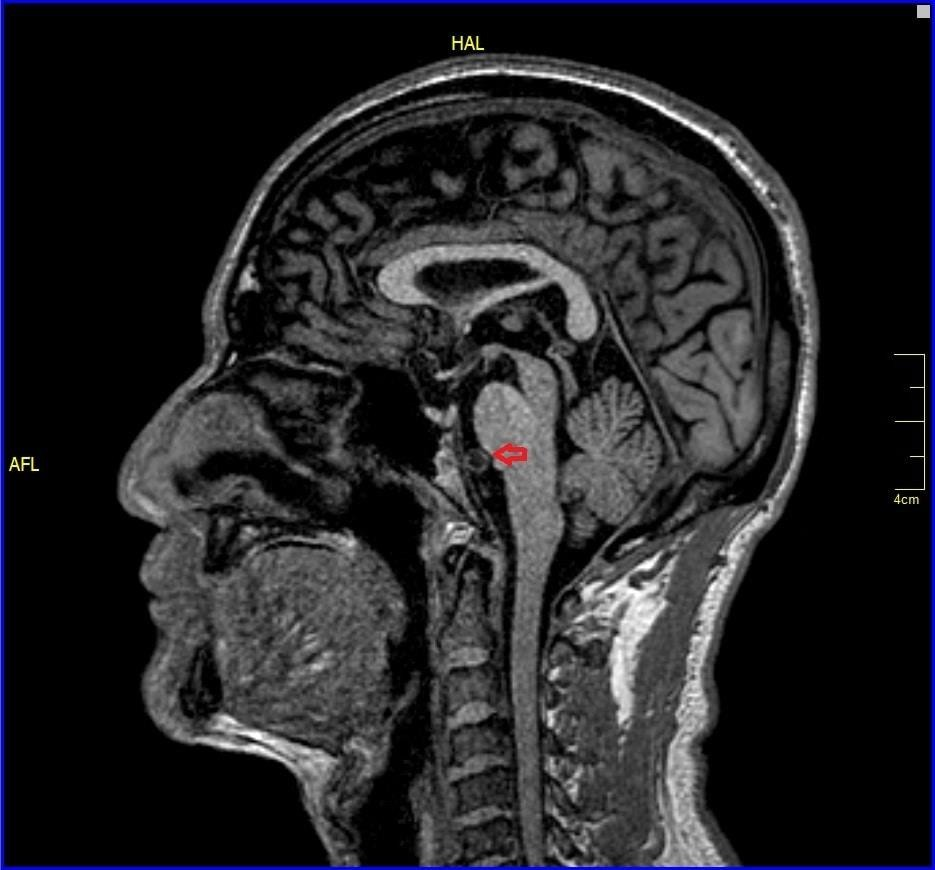

All other blood investigations including thyroid function tests and autoimmune screening were within normal limits. Plain computed tomography (CT) brain was done and revealed well-defined hypodensities seen in right lentiform nucleus chronic infarct.1 Otherwise, no intracranial haemorrhage and no acute ischemic infarcts seen at other areas. Brain magnetic resonance angiography (MRA) was ordered and it showed impingement of V4 vertebral artery to anterior lower pons near midline which is the exit of the left abducens nerve from the pons and also trigeminal nerve (blue arrow) and right abducens nerve (Figure 1-3) No abnormal signals were seen in brainstem. After ruling out other aetiologies of sixth cranial nerve, diagnosis of isolated sixth cranial nerve palsy was made.

Figure 1 CT brain showing right lentiform nucleus chronic infarct.